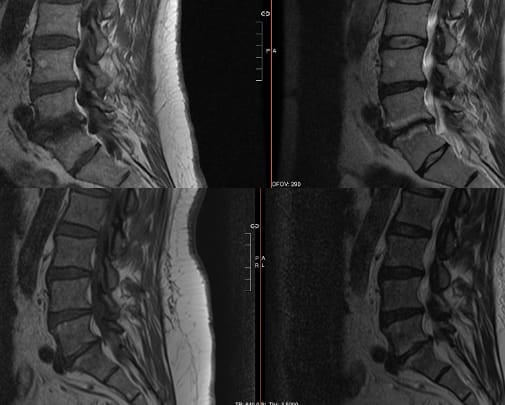

Vertebrogenic pain results from degenerative changes of vertebral endplates—the interface between intervertebral discs and vertebral bodies. Patients often describe deep, midline lumbar pain worsening with loading of the anterior spinal column: spinal flexion, prolonged sitting, bending, and lifting. Unlike facet-mediated pain, vertebrogenic pain is typically not influenced by lumbar spinal extension positions. The pathophysiology of this condition includes inflammatory and fibro-fatty changes, manifesting on MRI as modic changes: Type 1 (active inflammation, hypointense T1/hyperintense T2), Type 2 (fatty infiltration, hyperintense both sequences) (Figure 1).1,5-7 Neoinnervation of the vertebral endplates occurs via the basivertebral nerve; 90% of damaged endplates with Type 1 or Type 2 Modic changes demonstrate pathologic neural ingrowth compared to only 30% of annular tears. Immunohistochemical studies demonstrate the presence of substance P and protein gene product 9.5 within basivertebral nerve fibers, confirming their nociceptive function.1,5,8,9